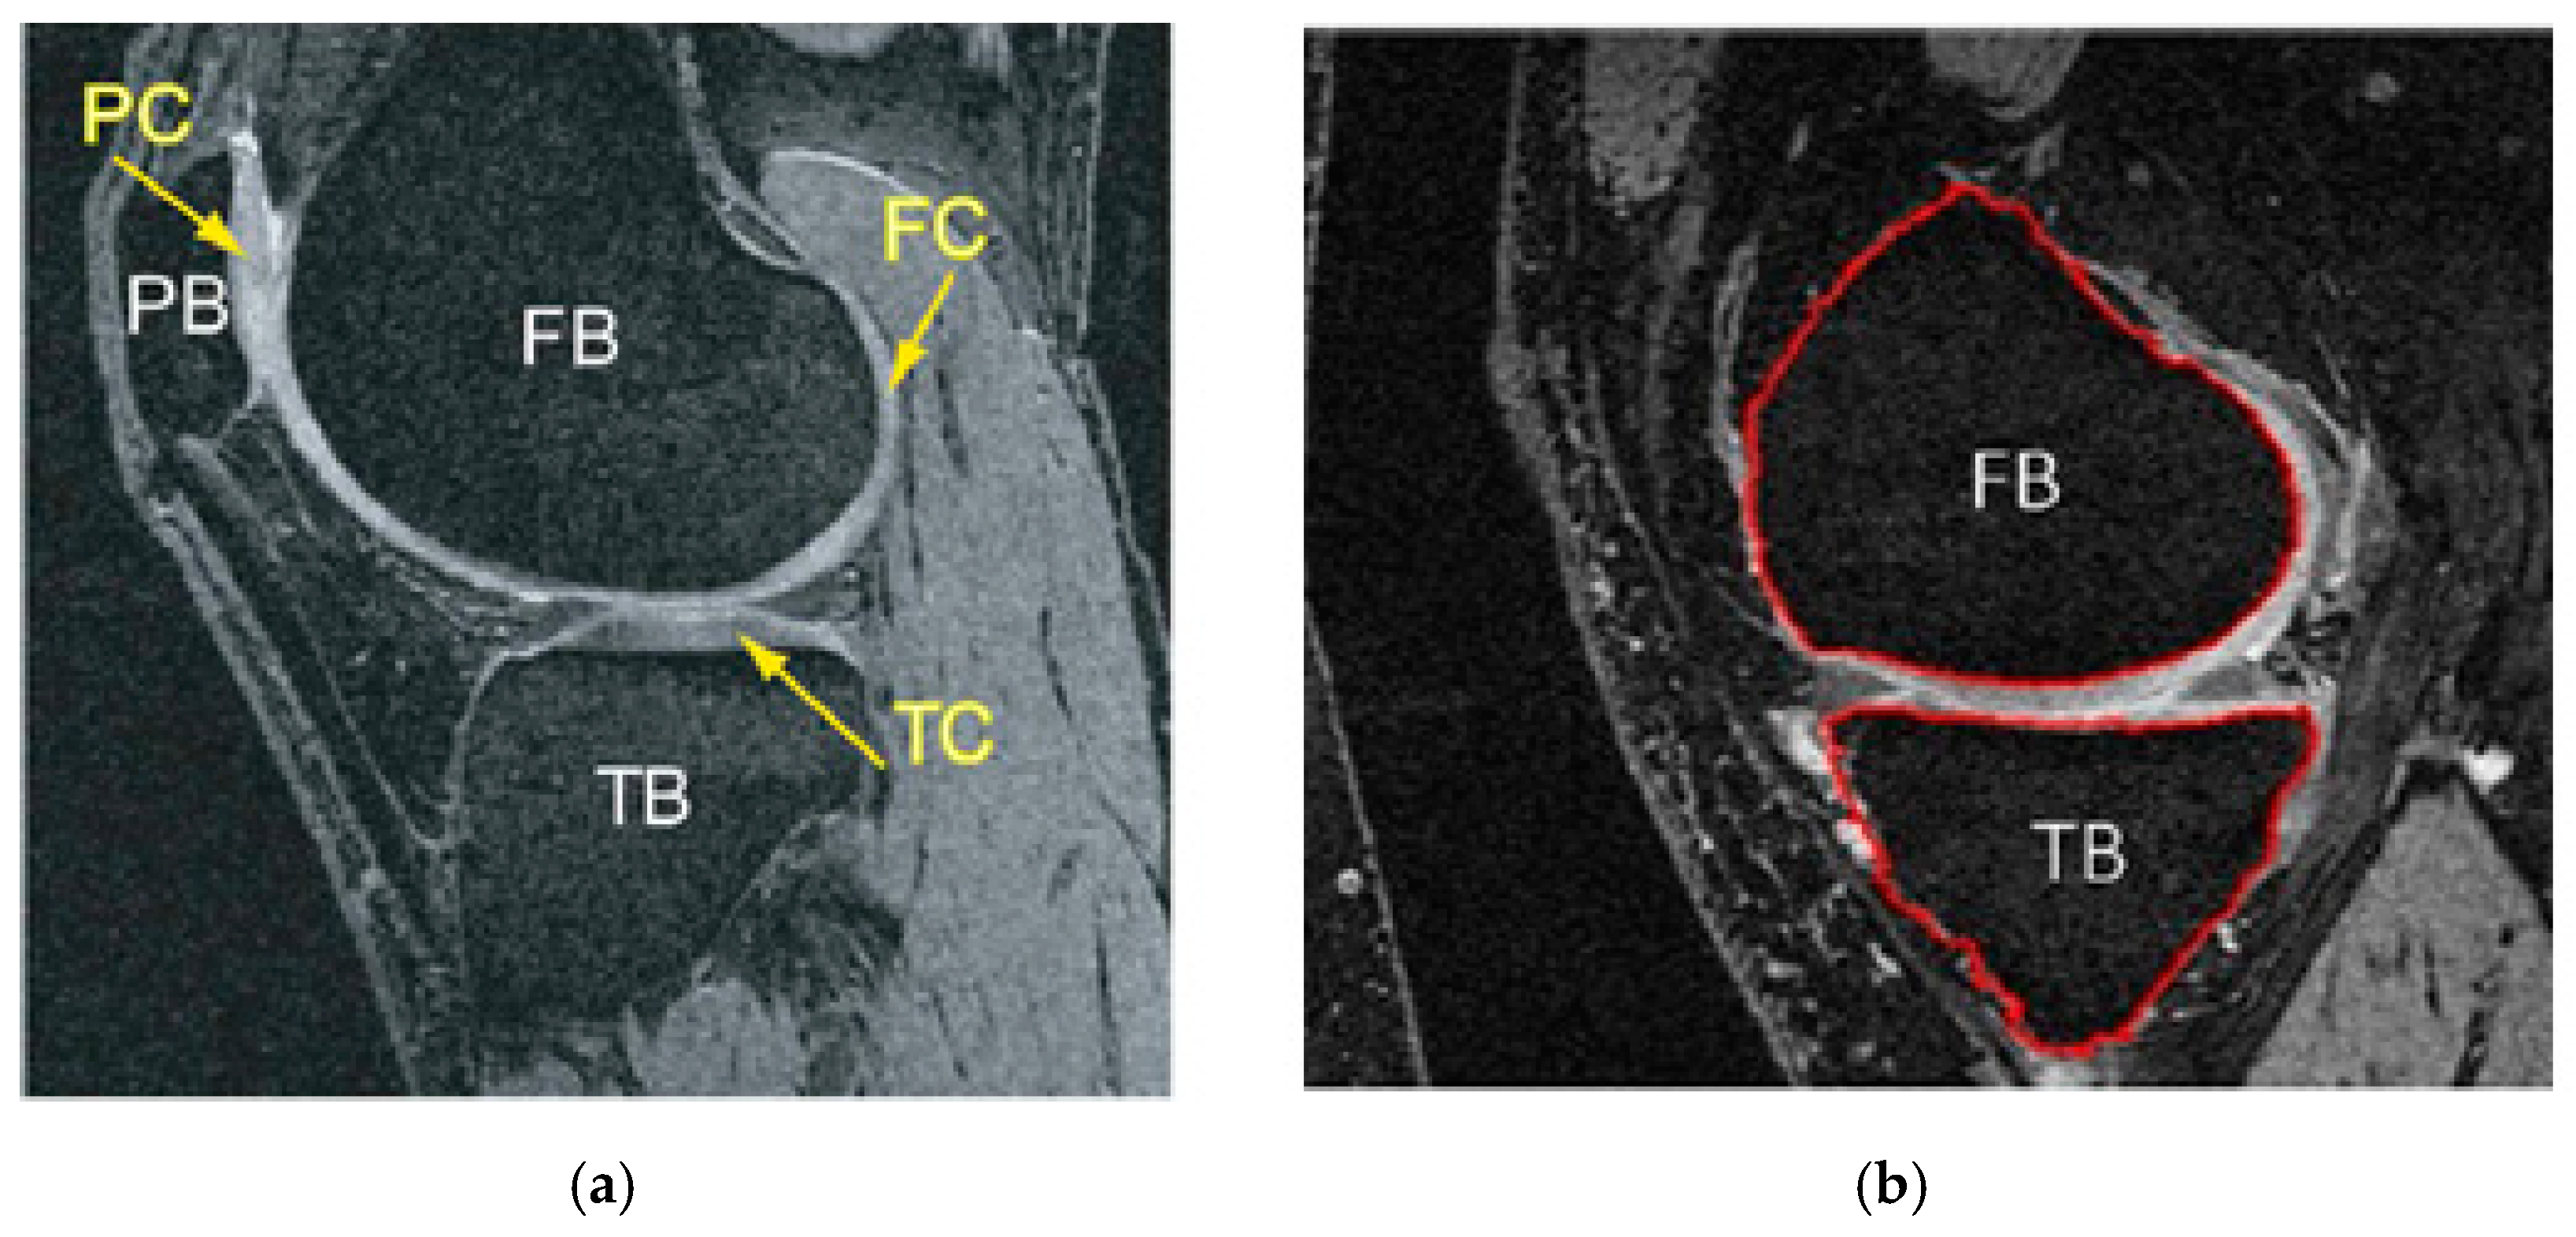

Osteoarthritis of the knee results in a constant loss of mineralization, causing its sensitivity to structural deformation [13]. Some structural changes can be seen on X-rays, including bone marrow lesions (BMLs), subchondral bone attrition (SBA), and osteoblasts, which are some of the radiologically apparent indicators of OA-related clinical studies. According to a study reported by (Hunter et al., 2006), subchondral BMLs are more evident across knee regions with increased biomechanical loading [14]. In contrast, other studies showed that the development of BMLs was associated with the loss of cartilage [13,15,16]. So, bone segmentation will be required for the detection and characterization of these biomarkers. Consequently, the following applications represent the goals of segmentation of the knee bone: firstly, to compute a bone model to investigate the effect of biomechanical stress at different localized knee sites; secondly, to quantify and monitor the changes of bone shape and surface associated with structural deformations; and finally, to produce a bone–cartilage interface (BCI) in order to extract cartilage tissue from the bone surface [15,17,18,19]. Figure 2 shows an example of a 2D bone structure and segmentation result.

Figure 2.

Knee bone segmentation has benefits over other tissues because of its location and anatomical size. (a) Illustrates the MR image of a knee joint—patella, femur, and tibia bones, readily apparent with the accompanying cartilage surfaces. TB = tibia bone, FB = femoral bone, PC = patellar cartilage, FC = femoral cartilage, TC= tibia cartilage. (b) Shows segmented tibia (TB) and femur (FB), which usually have better demarcation [19].